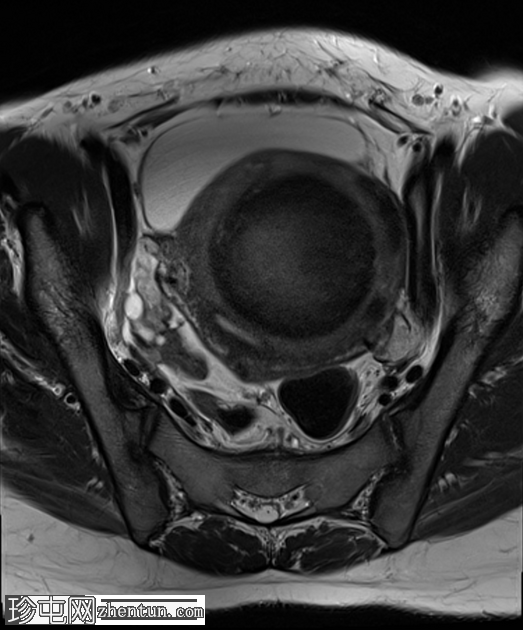

冠状位

T2加权像

子宫前壁可见一边界清晰的壁内病灶,大小约7.8 × 7 × 6.8 cm。脂肪抑制T1加权像呈弥漫性高信号,T2加权像呈高信号伴低信号环,无扩散受限及对比增强。

此外,可见一个2厘米的带蒂浆膜下肌瘤,以及较小的肌壁内和浆膜下肌瘤;所有肌瘤均呈均匀强化。

盆腔内可见少量游离液体,可能为生理性。